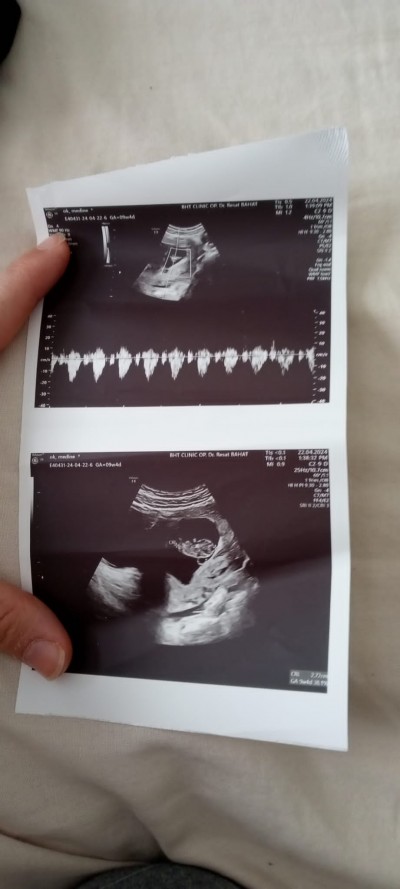

kızlar cinsiyet tahmini alabilir miyim

image

Gebelik haftası 9

Normalde yasak cinsiyet postu kapatırlar sohbet bölümünden sorun bana biraz saçma geliyor Dr görüp soylemedigini burda bizler nasıl bilicez ve şuan 9 haftalık ultrasonda bile gözükmez cinsiyet tam belirginlesmemistir bir buçuk ay daha sabredip 14/16 haftalarda ogrenirsiniz